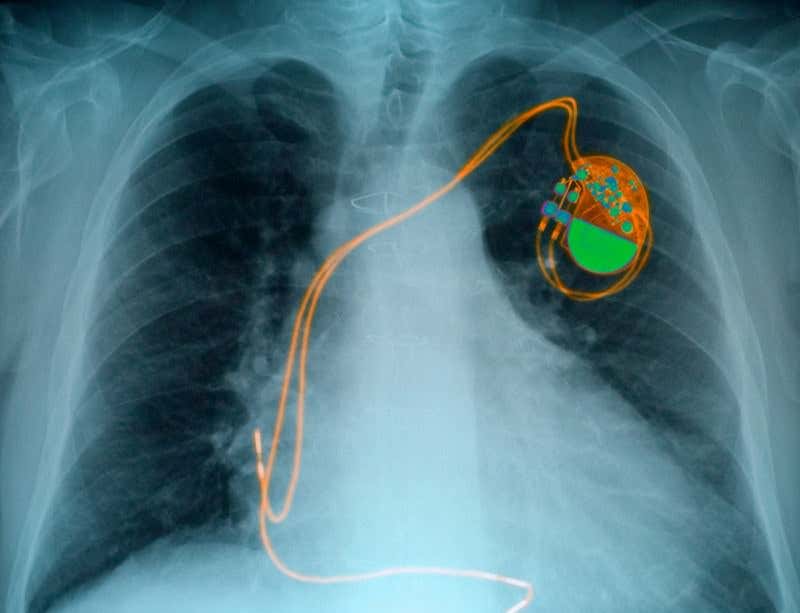

Soon it might be possible to ditch the hardware (Image: Kallista Images/Getty)

To return the heart’s electrical signals to normal, people with heart block are fitted with an electronic pacemaker. The device monitors the heart’s rhythm and sends corrective electrical pulses if it skips a beat or slows down.